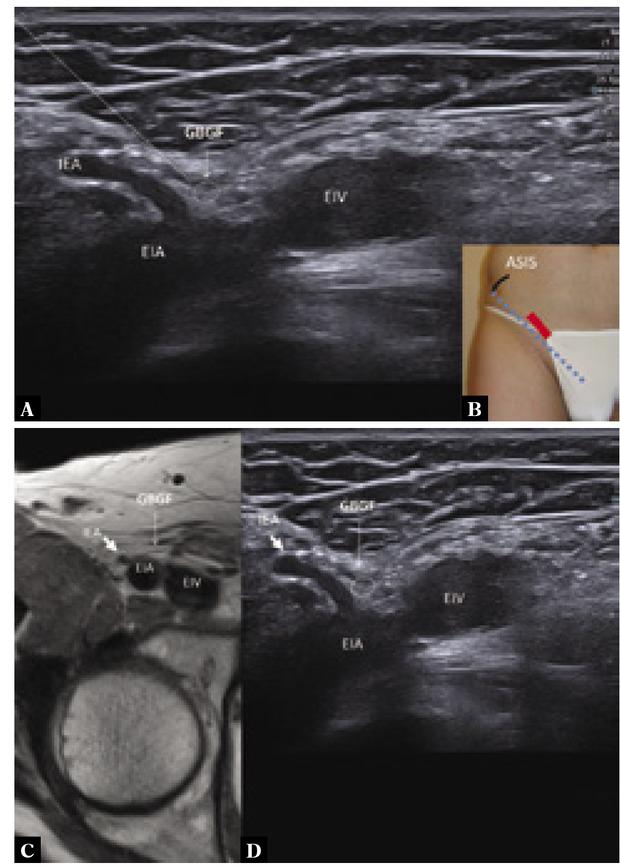

Fig. 2